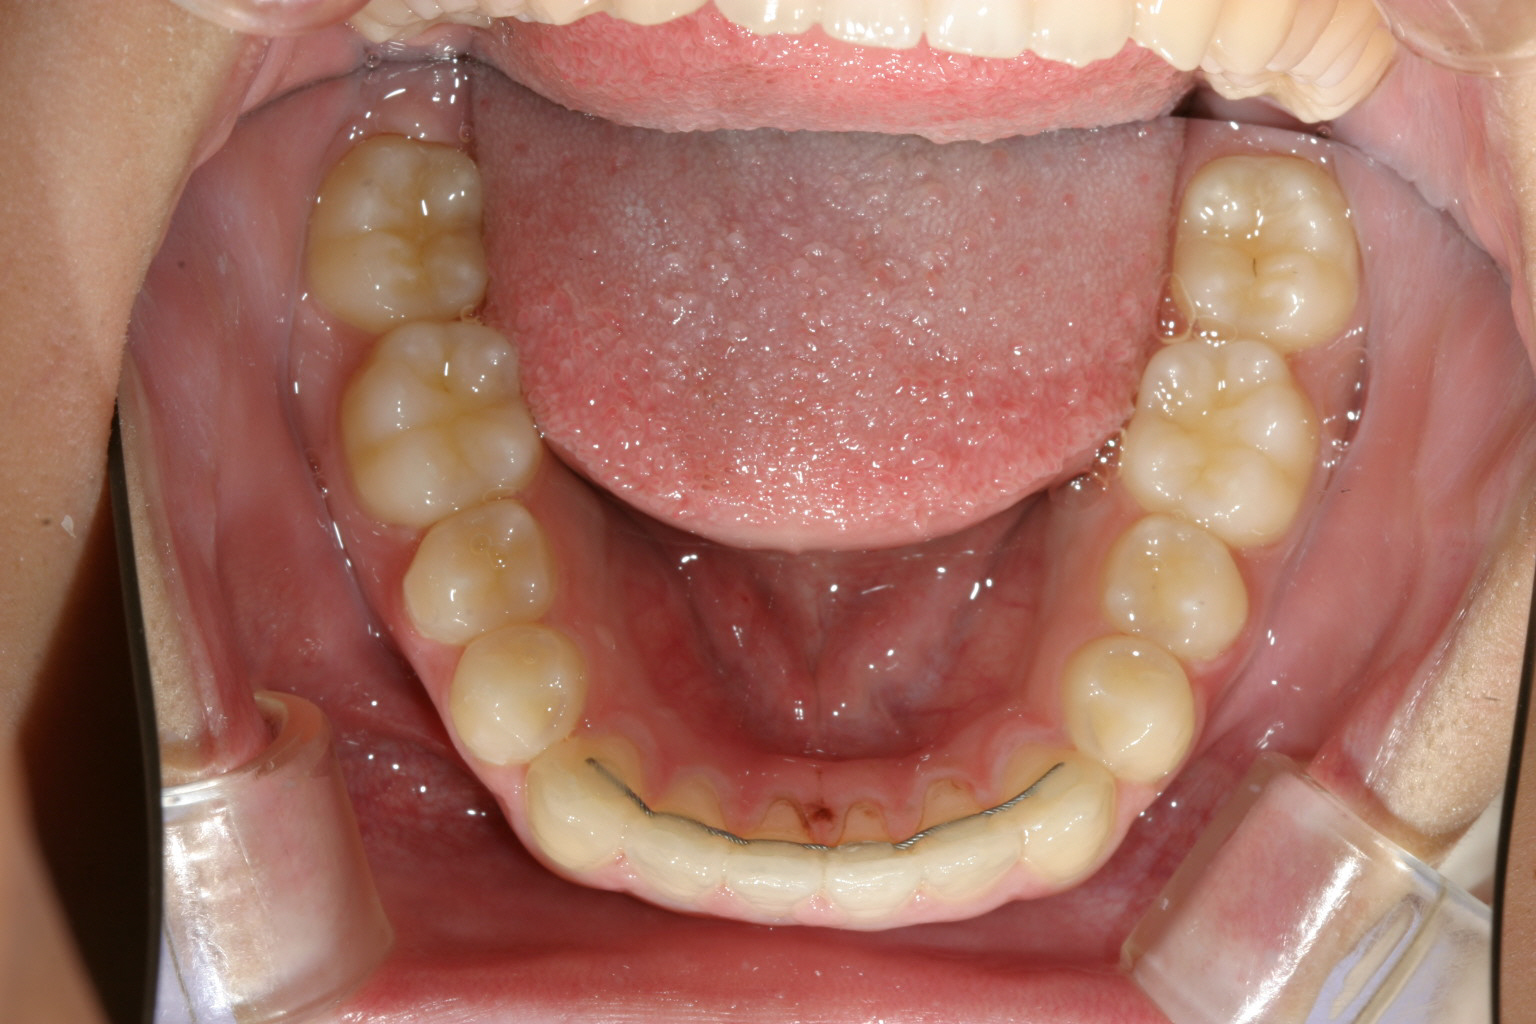

下顎の歯列は全然問題ないです。

下顎は問題なしです。